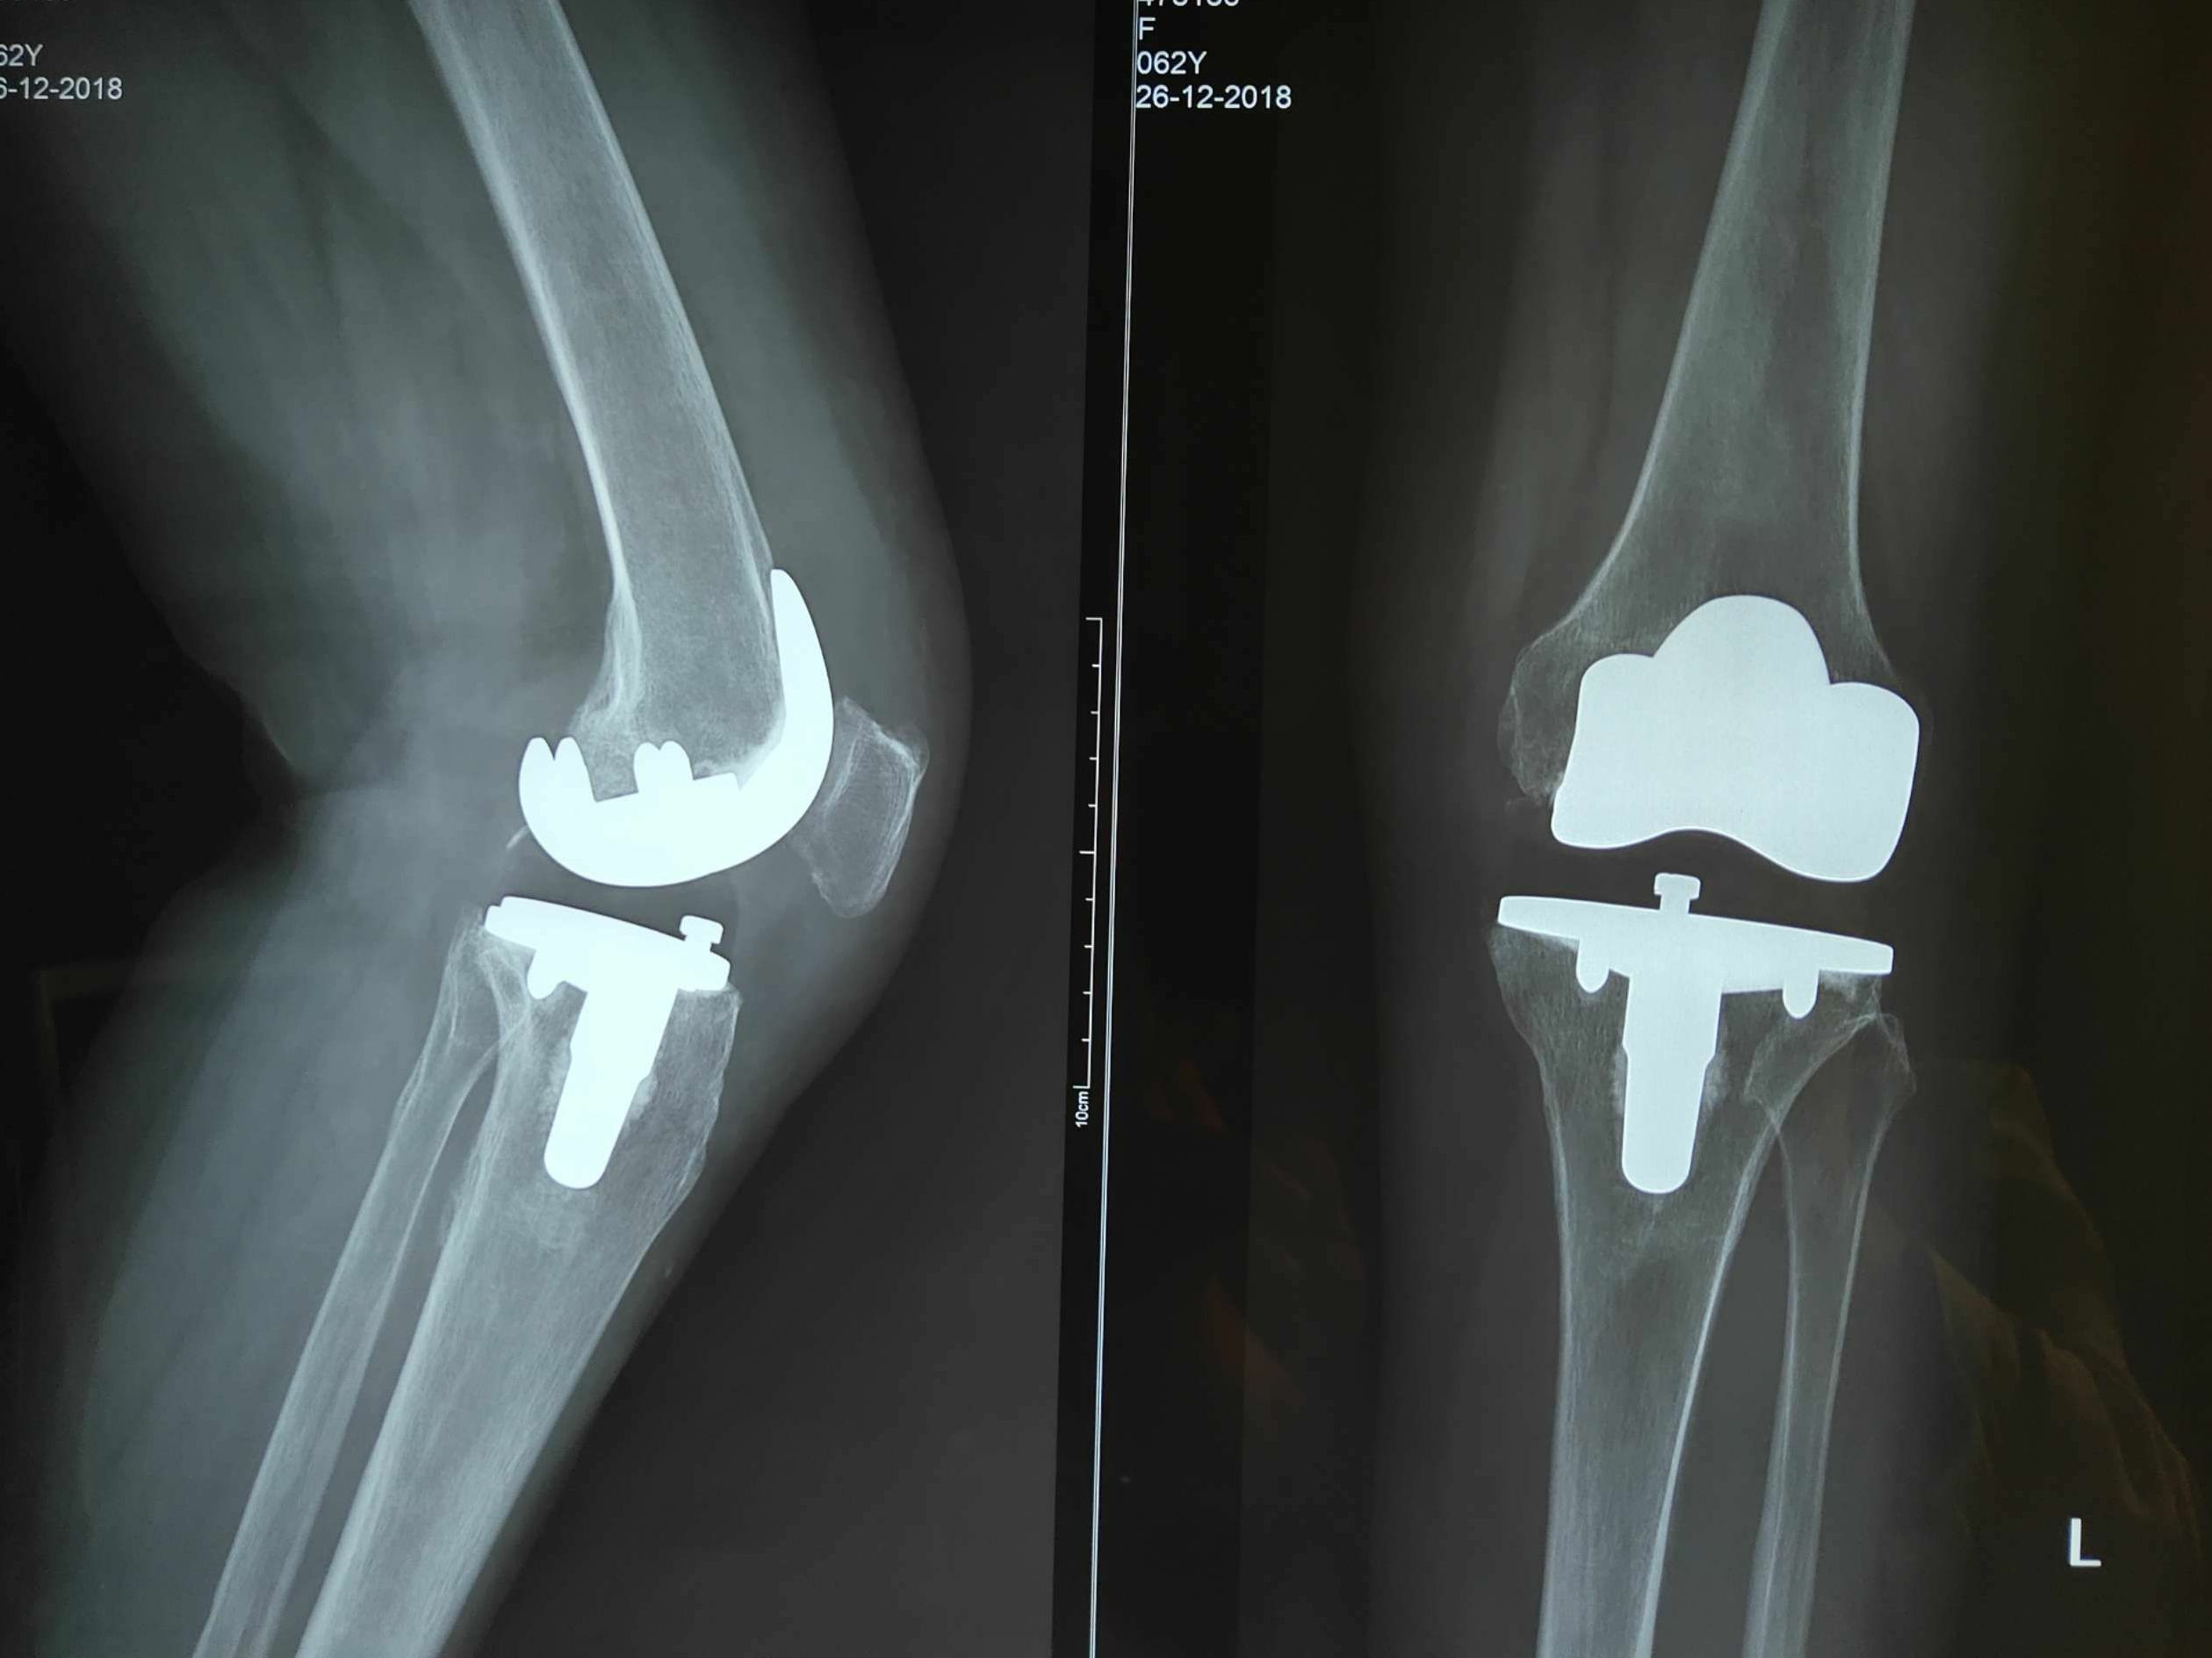

股骨头坏死是一个病理演变过程,初始发生在股骨头的负重区,应力作用下坏死骨骨小梁结构发生损伤即显微骨折以及随后针对损伤骨组织的修复过程。现在临床运用最多就是髋关节的人工置换,简单地来讲就是把坏死的股骨头去除掉,换一套人工的关节假体进去。

髋关节置换又称作人工髋关节置换,是将人工假体,包含股骨部分和髋臼部分,利用骨水泥和螺丝钉固定在正常的骨质上,以取代病变的关节,重建患者髋关节的正常功能,是一种较成熟丶可靠的治疗手段。

人工关节在国外始于40年代,我国在60年代以后逐步开展。早期只置换人工股骨头,俗称半髋置换,后发展至全髋关节置换。骨性关节炎丶股骨头坏死丶股骨颈骨折丶类风湿性关节炎丶创伤性关节炎丶良性和恶性骨肿瘤丶强直性脊柱炎等,只要有关节破坏的X线征象,伴有中度至重度持续性的关节疼痛和功能障碍,其它各种非手术治疗无法缓解者,都有进行髋关节置换术的指征。人工假体的材质随着科技发展有不锈钢丶钛合金丶陶瓷等多种。部分患者有手术后疼痛和明显的假体松动等。

人工髋关节置换是指用生物相容性和机械性能良好的材料制成的一种类似人体骨关节的假体,利用手术方法将人工关节置换被疾病或损伤所破坏的关节面,其目的是切除病灶,清除疼痛,恢复关节的活动与原有的功能。人工关节置换具有关节活动较好,可早期下地活动,减少老年病人长期卧床的并发症等优点。